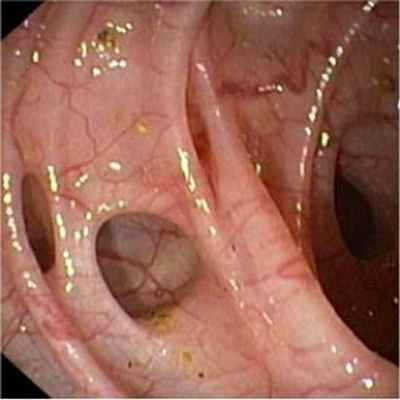

Основным диагностическим методом дивертикулярной болезни толстой кишки является фиброколоносокопия – внутрипросветный осмотр кишки, а также осмотр состояния слизистой у дивертикулов. Дополнительно может применяться ирригоскопия (осмотр на рентгенаппарате, после введения контрастного вещества в клизме). Также с целью уточнения применяются такие методы, как виртуальная фиброколоноскопия (когда осмотр проходит в аппарате МРТ, а компьютерная программа сама создает картинку кишечника в просвете).

Колоноскопия — то есть исследование толстой кишки при помощи гибкого аппарата с видеокамерой — тоже способ обнаружить дивертикулы. Большинство дивертикулов обнаруживают случайно именно при плановой колоноскопии, которую делают для раннего выявления рака. Однако при подозрении на острое воспаление дивертикула (дивертикулит), колоноскопию не используют как первоочередной способ диагностики. При колоноскопии кишку изнутри раздувают газом, а это может привести к перфорации (разрыву) дивертикула.